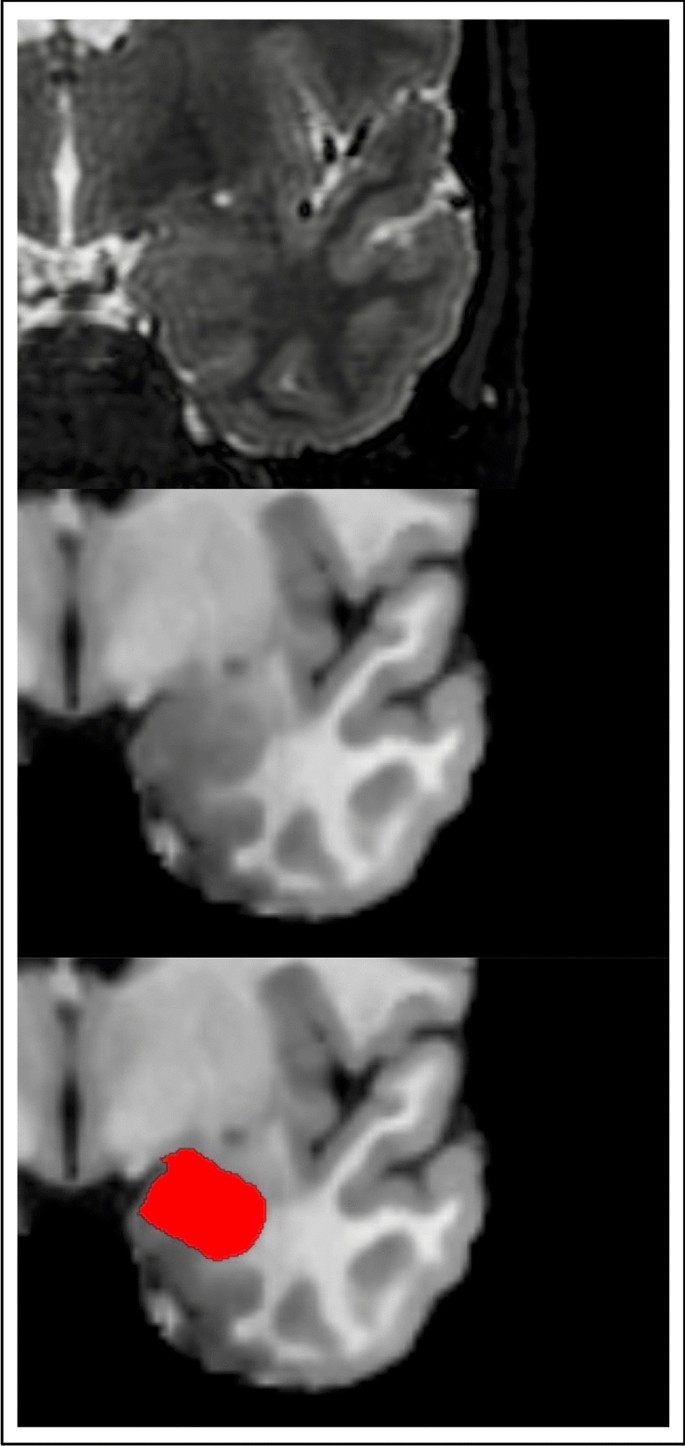

Automated FreeSurfer-based segmentation of the amygdala in structural MRI data is visualized in Fig. 1. First, we tested whether whole amygdala volumes are altered in VP/VLBW adults compared to FT controls using general linear models. Total intracranial volume (TIV), sex and scanner were entered as covariates. We found significantly lower left (p < 0.001) and right whole amygdala volumes (p < 0.001) in VP/VLBW individuals compared to controls. Figure 2a and Table S1 show estimated marginal means and p-values.

Segmentation of the amygdala. T2-weighted and T1-weighted images of the amygdala as segmented by FreeSurfer.

Images saved as DICOMs were converted to Nifti-format using dcm2nii80. MRI data were segmented using the FreeSurfer image analysis suite, version 6.0 (http://surfer.nmr.mgh.harvard.edu/). It includes a tool to produce an automated segmentation of the amygdala81. This atlas was created based on Bayesian inference using ultra high-resolution ex-vivo MRI data and evaluated by applying it to in-vivo MRI data of patients with Alzheimer’s Disease and patients with Autism Spectrum disorders as well as healthy controls81. Using both high-resolution T1-weighted and T2-weighted images, the function segmentHA_T2.sh generates whole amygdala volumes for the left and right hemisphere, respectively. Output segmentations were inspected visually. Amygdala segmentation is shown in Fig. 1. Successful segmentation of the amygdala was available in 101 VP/VLBW subjects and 109 FT subjects (see Fig. S1).